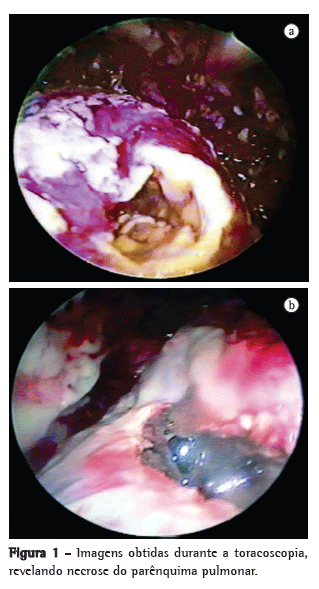

Estabelecia-se o diagnóstico de PN quando uma cavidade contendo detritos necróticos era encontrada no parênquima (Figura 1). Em tais casos, realizava-se desbridamento de todo o tecido necrótico e limpeza, e, para melhorar a drenagem, alargava-se a abertura da cavidade pulmonar.

ResultadosNecrose do parênquima pulmonar foi encontrada em 24 pacientes (46%).